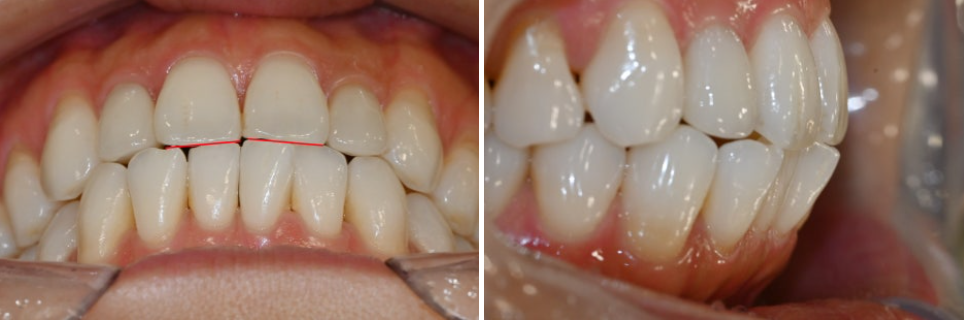

그러나 앞니는 절단면끼리 일자로

타이트하게 맞물리는 3급 부정교합인

절단교합 직전에 이르는 상태였습니다.

부분교정 치료가 끝나고 나서

가지런한 치열로 제자리를 찾아갔습니다.

이제는 어느 방향에서 보더라도

윗니가 아랫니를 살짝 덮고 있습니다.

원래 있어야 될 위치에 되돌려 놓으면서

치아 안쪽에는 재발 방지를 위한

얇은 철사(고정식 유지장치, fixed retainer)를

부착해뒀음을 확인할 수 있습니다.